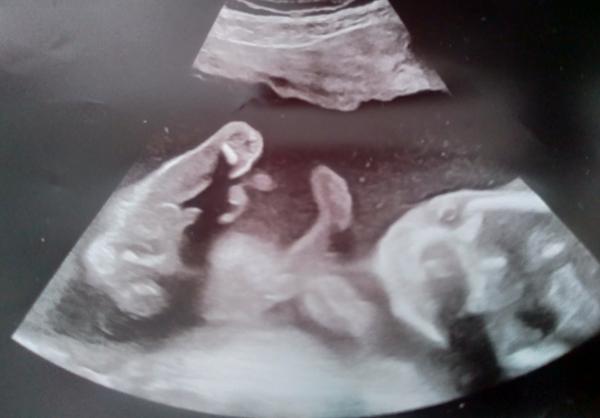

Foto z ultrazvuku. Holčička nebo klučík?

Hezký večer, dnes jsme byli na screeningu v prvním trimestru, paní doktorka nám řekla pohlaví s jistotou 90%, nicméně prý už se takhle jednou sekla, tak by mě, čistě ze zvědavosti, zajímalo, co myslíte vy? Mě to podle toho co jsem na internetu vyčetla sedí s paní doktorkou, ale víte jak, sem baba zvědavá 🙂

Rýpalky, prosím, nevyjadřujte se. Otevírám diskuzi vyloženě pro zábavu a zajímavost, jsem si opravdu vědoma toho, že mi na internetu, pohlaví dítka 100% neurčí. 🙂 díky